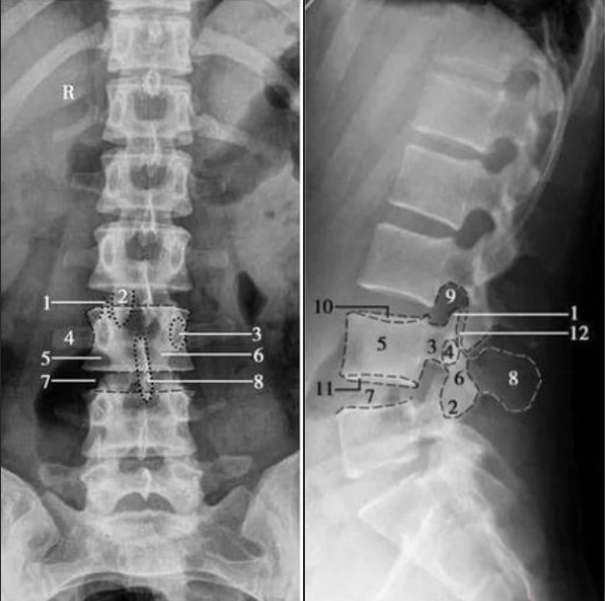

腰椎正侧位

1. 上关节突;2. 下关节突;3. 椎弓根;4. 横突;5. 椎体;6. 椎弓板;7. 椎间隙;8. 棘突;9. 椎间孔;10. 椎体上终板;11. 椎体下终板;12. 椎突间关节